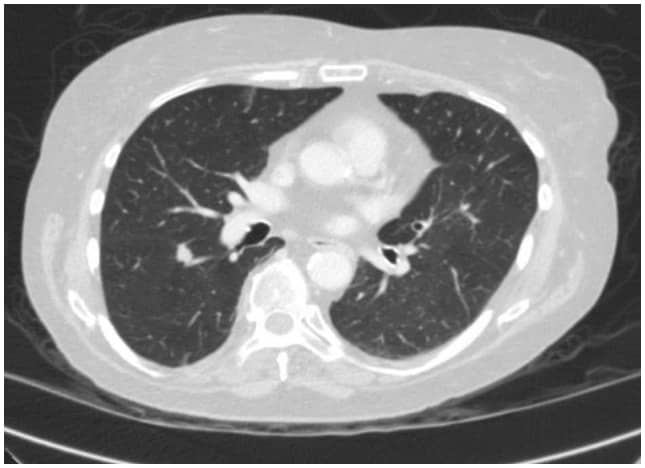

In questo caso, una TAC toracica ha rivelato una lesione spiculata di 1,3 cm sulla superficie fissurale del segmento superiore nel lobo inferiore destro, altamente sospetta di un carcinoma polmonare (Figura 1). Successivamente è stato effettuato un test PET/TAC che ha mostrato l'avidità di FDG sospetta di malignità.